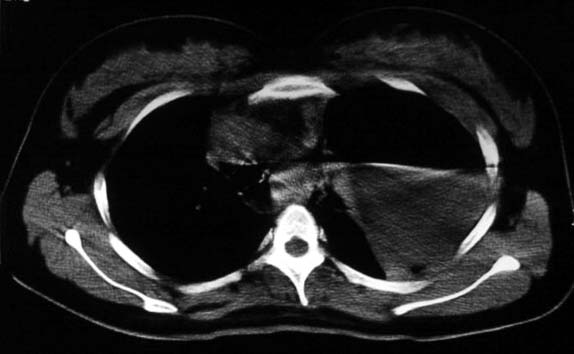

标题: CT5517:女性、24岁,反复胸痛、气促不能平卧半月。 [打印本页]

标题: CT5517:女性、24岁,反复胸痛、气促不能平卧半月。

左肺可见二个含气或液气的囊状影,左肺段支气管、左肺动脉显示不清,纵隔右移,考虑:左肺支气管肺囊肿,左肺发育不良,纵隔疝。

左侧气液腔与胃腔影相连,考虑膈疝。钡餐检查有助于诊断。

我看这是膈疝,在纵隔窗第六\\七幅图像上可见胃粘膜影,再者可见两个腔影,这在液气胸是不会有的.

支持膈疝,纵隔窗内可见消化道的内容物。

“反复胸痛、气促不能平卧半月”。+影像学表现=膈疝